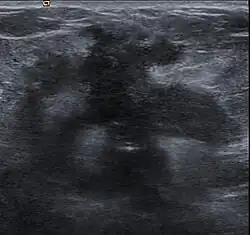

Breast cancer

Clinical presentation of a lump in the breast is histologically viewed as a collagenous tumor or desmoplastic response created by myofibroblasts of the tumor stroma.[18] Proposed mechanisms of activation of myofibroblasts are by immune cytokine signaling, microvascular injury, or paracrine signaling by tumor cells.[18]